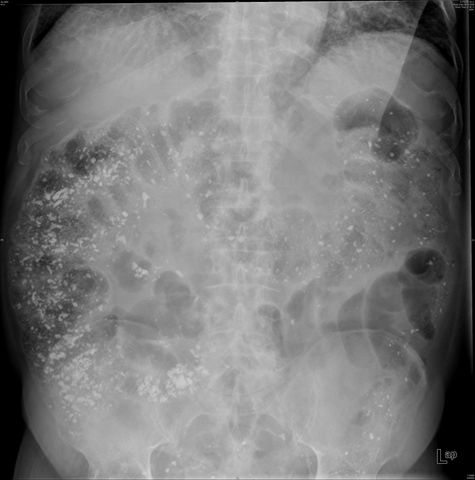

Dilatación colónica. Diverticulosis.